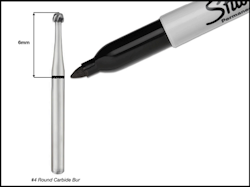

Round-type burs and/or straight burs with shorter working flute distances can be premeasured and marked with an indelible marker at the target vertical depth (Fig. 5). The other method involves the use of a periodontal probe and the periodic verification of depth as the bur is advanced toward the pulp chamber. In some scenarios, both methods may be indicated.